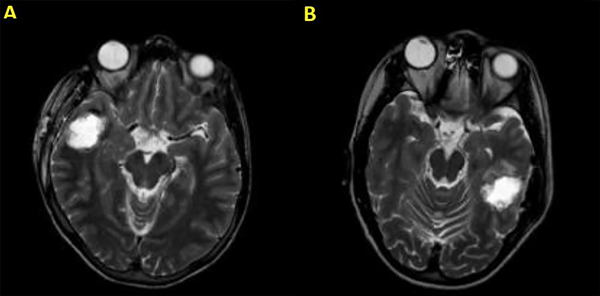

La amigdalohipocampectomía implica la eliminación del hipocampo, amígdala, uncus, giro parahipocampal y otras estructuras. No hay un método estandarizado para operar, pero las opciones incluyen lobectomía temporal anterior, amigdalohipocampectomía selectiva y amigdalohipocampectomía a través del giro temporal medio. Una craniotomía frontotemporal estándar comienza con una incisión en forma de signo de interrogación. Después de la apertura de la duramadre, se visualizan la cisura de Silvio, el giro temporal superior (T1) y el surco central. El primer paso en la amigdalohipocampectomía es penetrar al cuerno temporal del ventrículo lateral y eliminar el abultamiento del hipocampo en su superficie interna. El surco ventricular lateral es la entrada al giro parahipocampal, donde se realiza una resección subpial como primer paso quirúrgico (Figura 8). Luego, el hipocampo se puede mover lateralmente al espacio creado por la eliminación del giro parahipocampal para aspirar la fimbria de la piamadre subyacente. El hipocampo se elimina en un solo bloque. La resección anterior para lograr una amigdalohipocampectomía incluye la resección completa del uncus (Figura 5-7).23,24,25

Figura 7. Ejemplo de una amigdalohipocampectomía selectiva postoperatoria en un paciente con convulsiones persistentes. A y B muestran una vista sagital del enfoque, mientras que C y D desde la base.